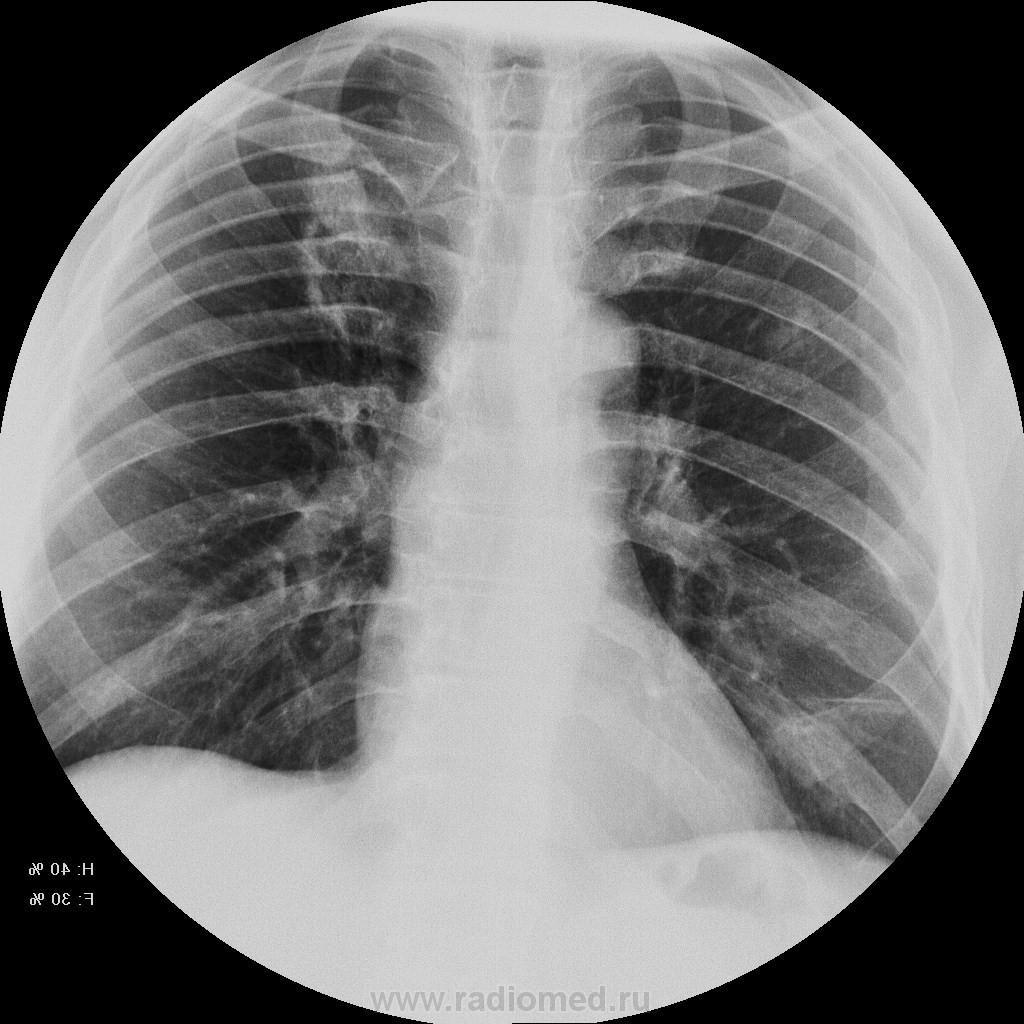

Пациет 60 лет после перенесения ОНМК. жалоб нет ( по легким) . СОЭ, лейкоциты, HB в норме.

Какие будут мнения.

КТ еще не запущен - так что выжимаем все из линейки...

Туберкулез под (?)

У больных с последствиями ОНМК следует думать об аспирационном генезе заболевания. В пользу этого свидетельствует поражение задних сегментов и двусторонняя локализация изменений.